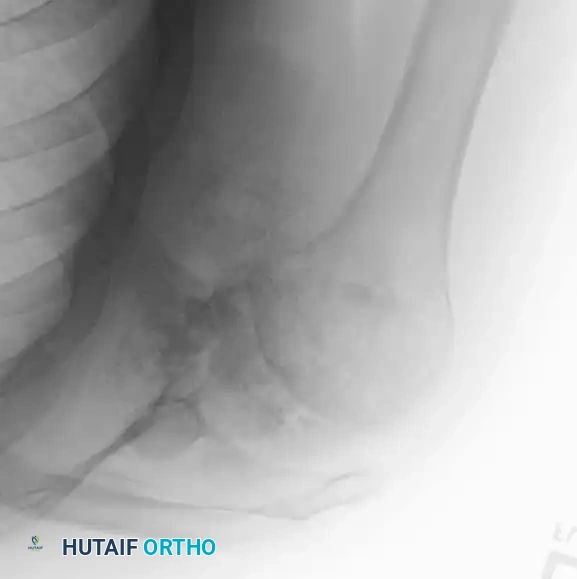

BENIGN TUMORS AND TUMOR-LIKE LESIONS Surgical Diagram

Radiograph and MRI of a shoulder with synovial chondromatosis, demonstrating multiple intra-articular ossified loose bodies. The gross specimen photograph highlights the sheer volume of cartilaginous bodies resected during synovectomy.